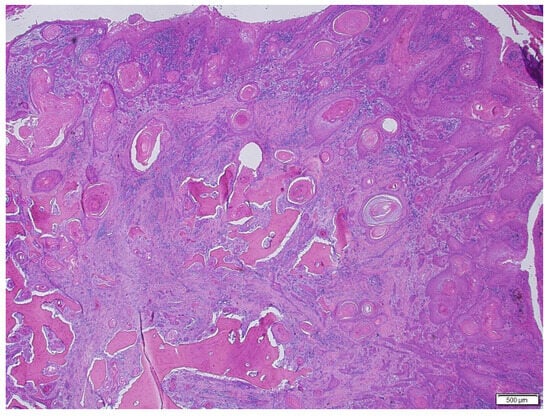

3. Results